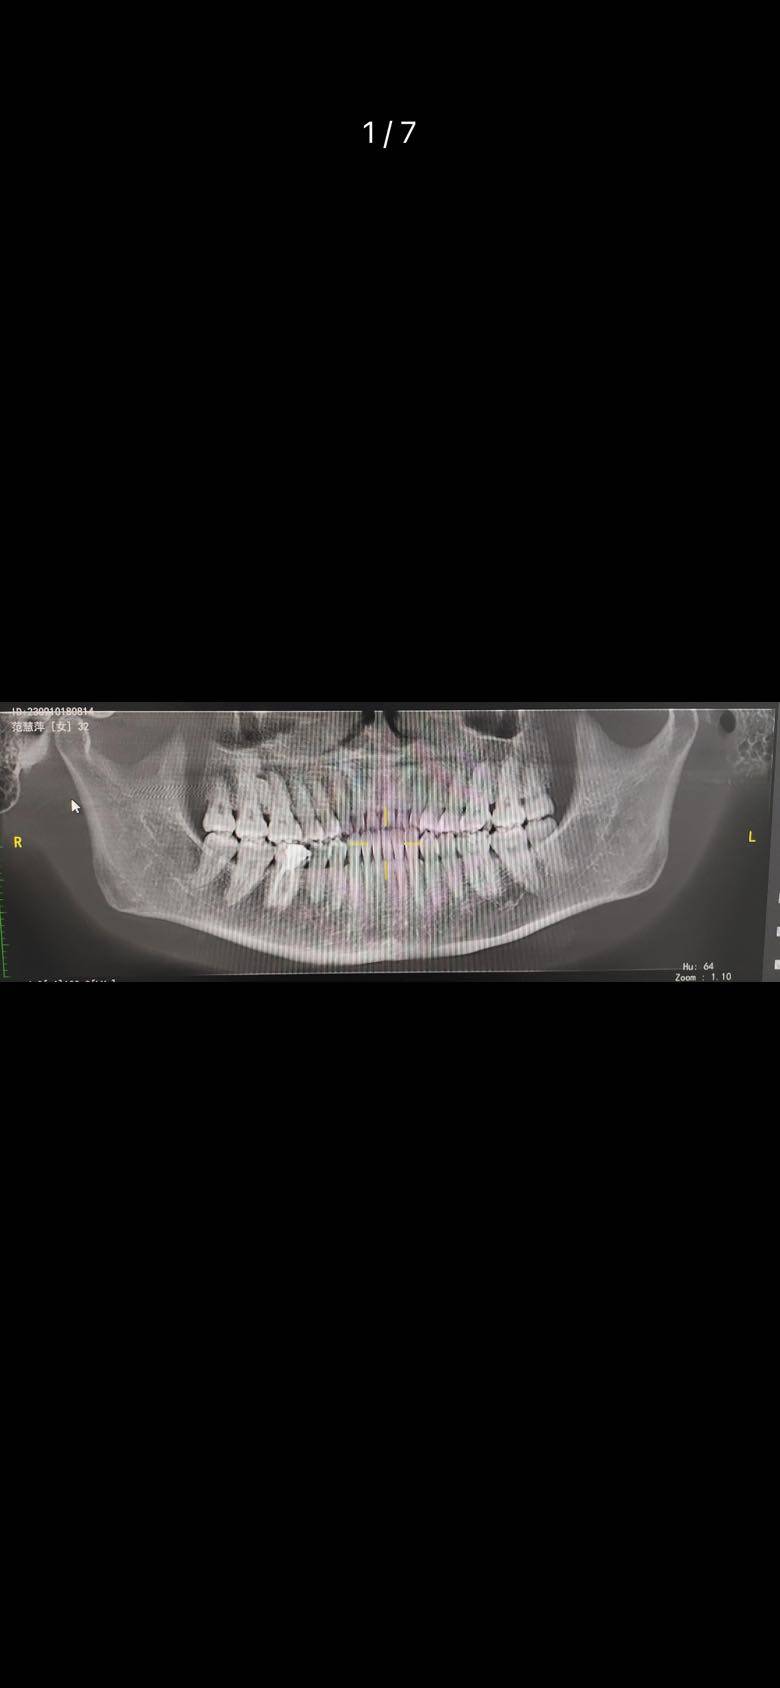

这个月还配了新眼镜,洗了牙,感觉干了不少事情,因为牙疼怕牙齿坏了,正好洗牙检查一下牙齿问题,因为我的牙齿不太好,已经修补了四五颗了,还好没啥问题就放心了